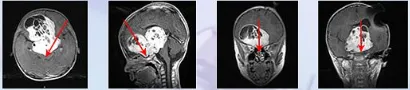

北京天坛医院联合INC巴特朗菲教授展开强强合作。术中发现,肿...